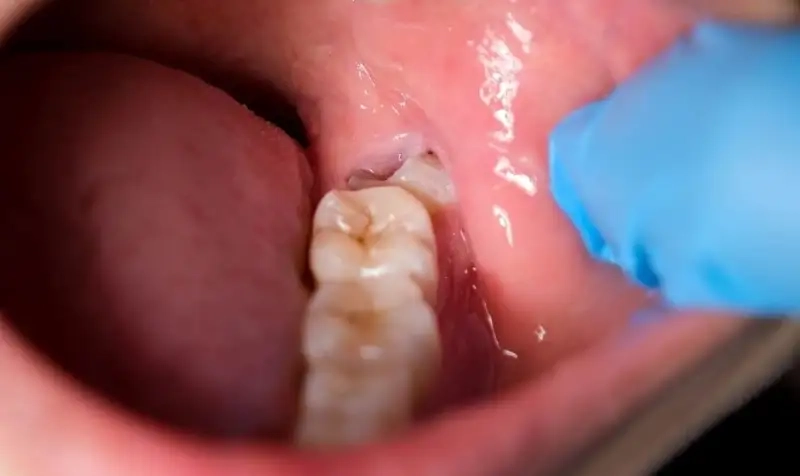

Các biến chứng thường gặp khi mọc răng khôn bao gồm viêm lợi, sâu răng số 7 kế bên, hình thành u nang hoặc áp xe quanh chân răng.

Nhổ răng khôn là phương án thường được áp dụng khi răng số 8 mọc lệch, gây đau nhức kéo dài, viêm lợi hoặc nguy cơ nhiễm trùng. Trong nhiều trường hợp, răng khôn mọc ngầm còn có thể làm xô lệch răng bên cạnh, ảnh hưởng đến khớp cắn và vệ sinh răng miệng.

Bác sĩ nha khoa sẽ tiến hành thăm khám, chụp X-quang để đánh giá vị trí, mức độ mọc lệch cũng như tình trạng sức khỏe tổng quát trước khi đưa ra chỉ định nhổ bỏ hay tiếp tục theo dõi định kỳ.